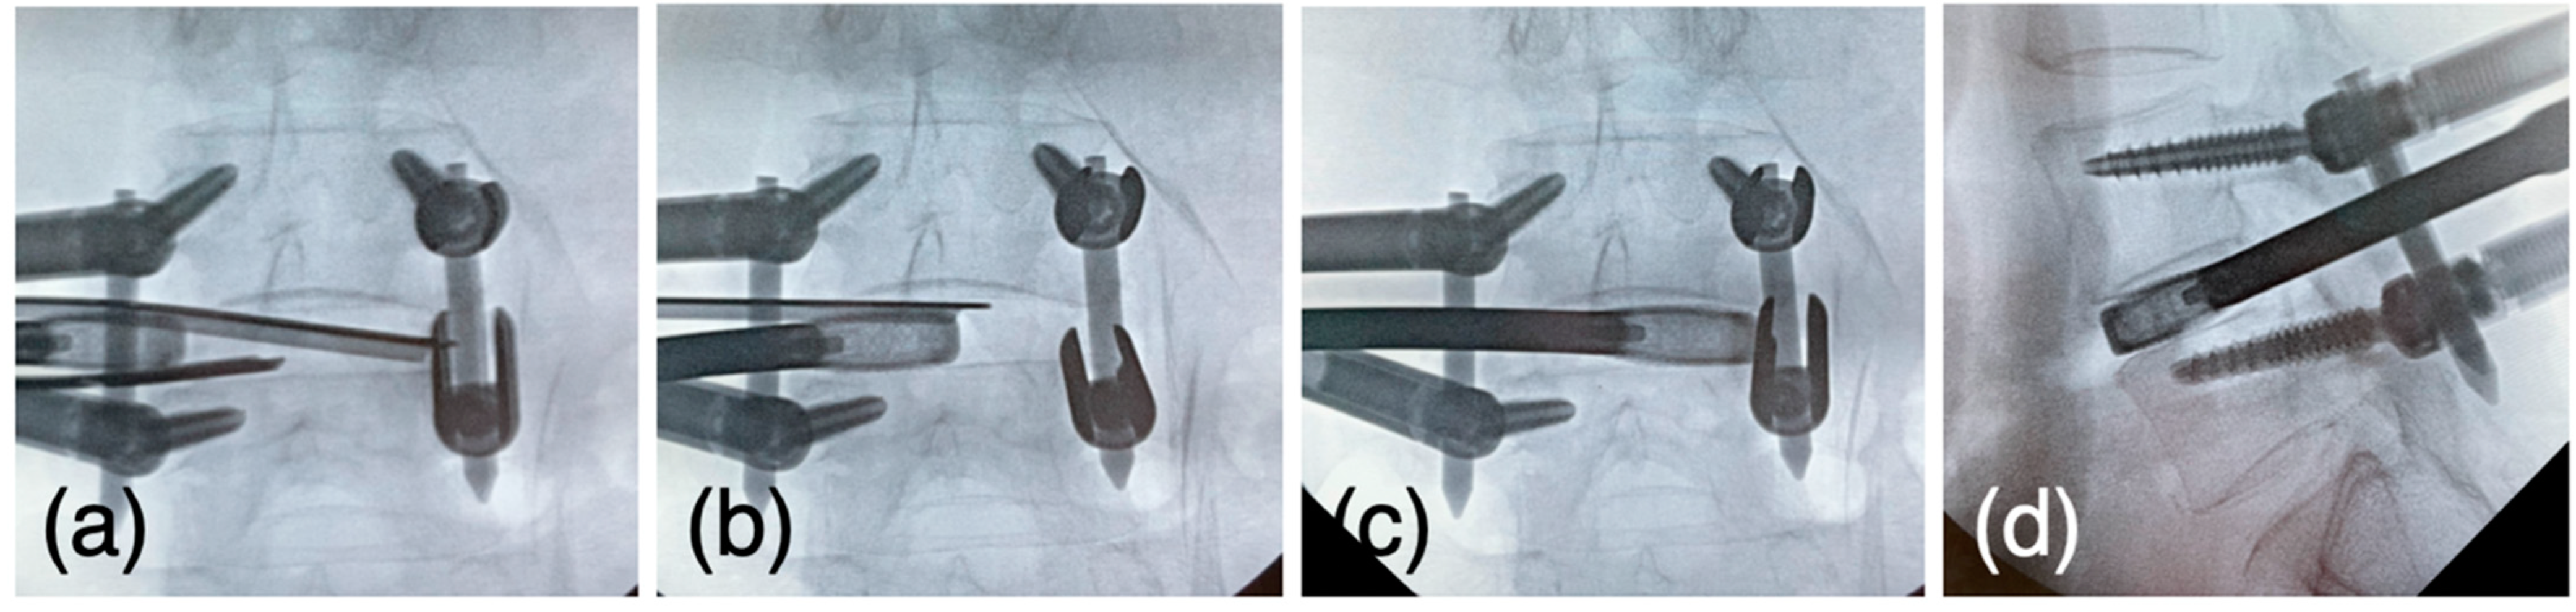

Figure 6.

(a) The pairs of J-shaped nerve retractors were set through the U-shaped sleeve (b) The cage is driven toward the disc space while placed between the retractors. (c) The sleeve is removed when the cage passes the exiting nerve root, and the cage is driven to the contralateral border of the disc space. (d) The lateral view confirms the cage set on the rim.